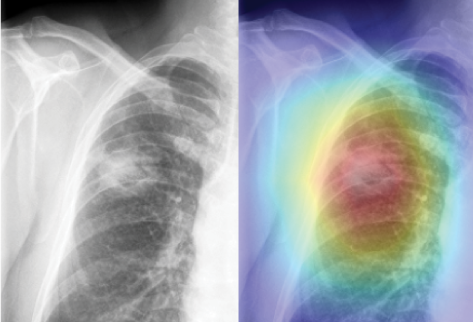

| ▲출처=루닛 인사이트. |

'루닛 인사이트'는 흉부 단순촬영(X-ray) 영상에서 폐 결절이 의심되는 부위의 정도를 색깔 등으로 표시해 의사의 폐결절 진단을 도와주는 소프트웨어다.

임상시험 결과 진단에 대한 정확도는 기존 방식 보다 4.8%로 높게 나왔으며 이번 개발로 CT 등 촬영 비용이 절감될 것으로 예상되고 있다.